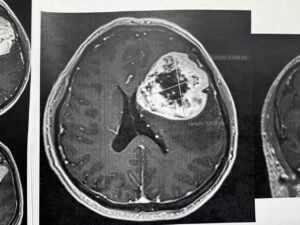

Para determinar la realización de este procedimiento y conocer el origen de los síntomas, explicó, el equipo médico del Instituto le realizó al derechohabiente estudios de tomografía y resonancia magnética.

“Se realizó tomografía de cráneo y, ante los hallazgos, se le practicó una resonancia magnética; posteriormente, se le detectó un tumor de características malignas en la región frontal premotora izquierda”.